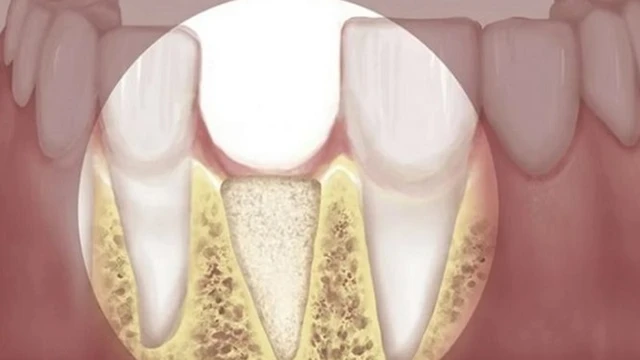

Tiêu chân răng là một trong những bệnh lý về răng miệng gây ảnh hưởng đến chức năng nhai khi ăn uống. Điều này không những làm giảm tính thẩm mỹ răng miệng mà còn gây cản trở đến việc phục hình răng về sau. Hãy cùng Long Châu tìm hiểu về bệnh lý này nhé!

/https://cms-prod.s3-sgn09.fptcloud.com/tieu_xuong_rang_nguy_hiem_nhu_the_nao_den_suc_khoe_S_Hj_QR_1680281916_3bb85dd0db.jpg)

Mất xương hàm sau khi mất răng là một hậu quả nghiêm trọng, gây ảnh hưởng đến tính thẩm mỹ và chức năng ăn nhai. Điều này có thể gây ảnh hưởng nghiêm trọng đến bệnh lý tiêu xương ổ răng. Vậy tiêu xương răng nguy hiểm thế nào đến sức khỏe?